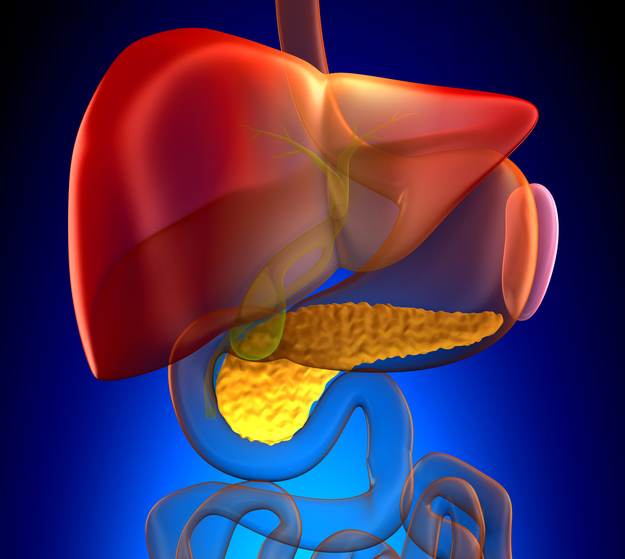

Bile is produced by the liver and is used to aid in proper digestion. It helps the body eliminate waste from the blood. The salts found in bile can emulsify fat and break it down into smaller particles. Bile can help the body absorb those broken down products of fat within the gut. As mentioned, bile is ...click here to read more